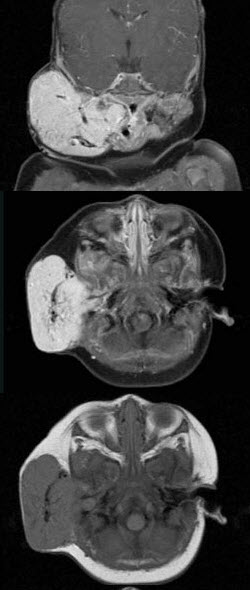

- 单项选择题老年患者,右侧面部肿胀,呈青紫色,MRI检查如图所示,请选择最可能的诊断()。

A、血管瘤

B、囊肿

C、脓肿

D、神经纤维瘤

E、神经鞘瘤

- A